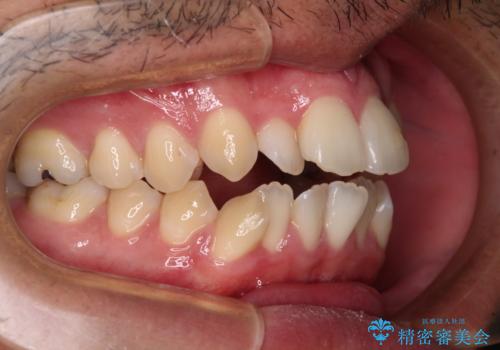

開咬とデコボコを整える インビザライン矯正治療

- 前歯の開咬と叢生を気にして来院された患者様です。

開咬の治療は、前歯を閉じるように動かすとともに、上下臼歯を圧下(骨内にめり込ませる)させることで進めて行きます。

インビザラインは臼歯の圧下を効果的に行えるため、インビザラインを用いて矯正治療を行うこととしました。また、アンカースクリューを用いて、口元の突出感の改善を図りました。